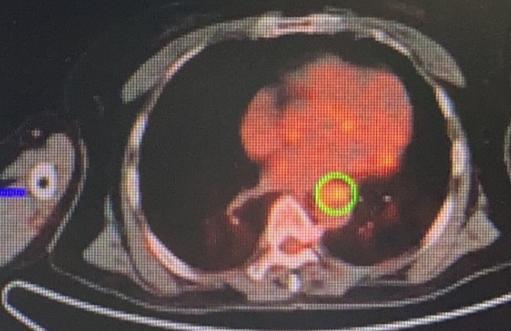

门诊一位65岁的农村阿姨,真的特别有健康意识!虽然身体一直挺硬朗,但她每年都会主动做胃镜检查。她父亲当年七十多岁因为食管癌去世,这件事她一直记在心里。 阿姨跟我说:“乔医生,我们农村人懂得不多,但听人说这个病有遗传的可能,我就上了心。每年不查一次,心里就不踏实,觉都睡不好。” 其实家里孩子不太理解,觉得她太紧张、浪费钱,可她就是坚持自己的习惯。 结果今年胃镜查出来,食管上有个小溃疡,阿姨自己上网查资料,看到我的科普,马上就来门诊找我了。后来取了活检,证实确实是早期食管癌。 幸运的是,全身检查下来没有发现转移,肿瘤也非常小,完全可以手术切除。 我们给她做了胸腹腔镜联合的微创手术,创伤小、恢复快。手术第二天,阿姨就能自己下床活动了,精神状态很好。 这件事让我特别感慨:肿瘤不怕发现得早,就怕发现得晚。早发现、早处理,不仅效果好,病人恢复也快,甚至能达到根治。 所以说,健康这件事,多一分谨慎总是好的——这位阿姨的“谨慎”,真的救了她自己。[作揖][玫瑰]